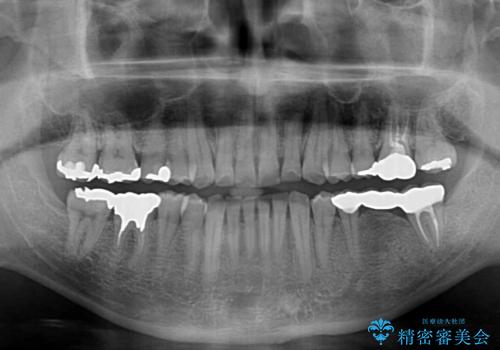

まずは奥歯の痛みを改善し、その後矯正治療を行い、最後にオールセラミックブリッジによる補綴治療を行うこととしました。

むし歯をきっかけに矯正治療を行うこととなりましたが、学生の頃から気になっていた歯列を改善することができ、患者様には大変満足していただけました。